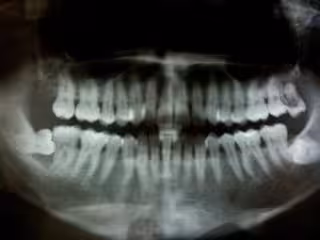

La enfermedad de las encías (gingivitis) que no se trata puede convertirse en periodontitis. Cuando esto sucede, la infección que afecta las encías causa la pérdida del hueso que soporta los dientes. La periodontitis es la principal causa de pérdida de dientes en los adultos y, además, también puede ser un factor de riesgo para el desarrollo de demencia, según han demostrado investigadores de la Universidad Nacional de Seúl (Corea del Sur).